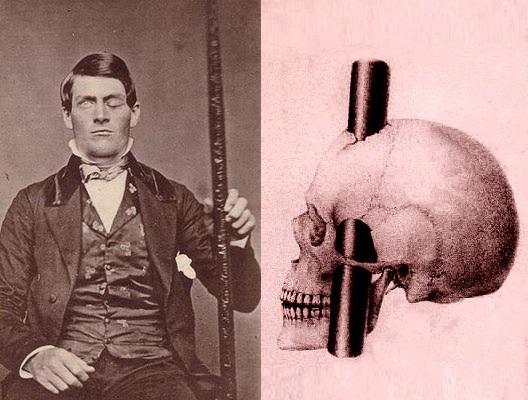

На заре 19 века некий американский строитель железных дорог, Финеас Гейдж стал известен, выжив после страшной травмы, когда железный прут прошел насквозь его мозг.

Эта ужасная трагедия произошла 13 сентября 1848 года.Финеас работал в бригаде, которая прокладывала железную дорогу сквозь скалу, в скале бурили скважину, туда укладывали взрывчатку, сверху засыпали песком и плотно утрамбовывали с помощью железного шести килограммового шомпола. Из-за невнимательности рабочих в скважину не засыпали песок, и когда пришло время работать шомполом, задев скалу, вспыхнула искра, следствии чего произошел взрыв подрывного устройства. Тот самый шести килограммовый шомпол отлетел от скалы и пробил голову Гейджа насквозь. Пострадавшего строителя откинуло на спину, он конвульсивно дергался, но чудом, через несколько минут встал и смог говорить.

Левая передняя головня доля головного мозга Гейджа была почти полностью уничтожена. Однако он находился в полном сознании. Его восстановление протекало весьма трудно. Все думали, что он не выживет, но 7 октября он поднялся с постели. Спустя месяц Гейдж расхаживал по дому и даже гулял на улице. Головная боль его больше не тревожила.

Напоминанием о случившейся трагедии, стала огромная вмятина в левой части головы и ухудшившееся зрение левого глаза. Не отразившись на физическом здоровье, травма повлияла на душевное состояние. Как упоминали его коллеги и знакомые, он стал грубее, вспыльчивее и более раздражительным к окружающим его людям.

После случившейся трагедии Финеас Гейдж прожил еще 12 лет, и скончался от приступа эпилепсии.В мае 2012 года американские ученые неврологи, опираясь на случай Геджа, что повреждение лобных долей оказывает сильное влияние на эмоции и личность, то есть приводит к изменению поведения человека.